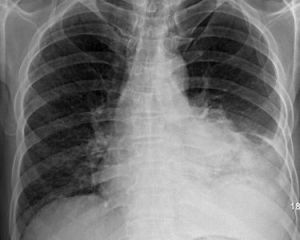

在X線胸片檢查發現的呼吸系統單發腫瘤中,良性腫瘤占8%~15%,成人氣管內的原發腫瘤很少見,且多為惡性,而在兒童中,多為良性。X線胸片及CT檢查是主要的發現及診斷手段,其可大致了解腫瘤的特性,如:鈣化、邊界、生長速度及與支氣管的關係等,最後確診常須術後病理組織學檢查。

X線胸片見邊緣清晰、光滑、密度較高的球形陰影,有時在病源內可見鈣化點。

1、X線檢查 中心型良性腫瘤胸片很少見到瘤體,偶見肺門圓形陰影,多僅能顯示其繼發的肺部病變,如:肺不張、阻塞性肺炎等。氣管正側位像有助於發現、定位氣管內腫瘤,以側位像更為清晰。周邊型良性腫瘤的胸片為:邊緣清晰、密度均勻、緻密腫物影,無空洞,偶見鈣化。

2、胸部CT或體層檢查 中心型良性腫瘤多可清楚地顯示瘤體,明確其部位、大小、管腔阻塞的程度及腫瘤累及的範圍。周邊型良性腫瘤因良性腫瘤的成分多樣性,故結節的密度不勻,CT值可在-100~ 150HU,故CT值的標準差多>30HU;而惡性腫瘤多因瘤體組織成分單一,故結節密度均勻,CT值多在35~55HU,標準差<30。